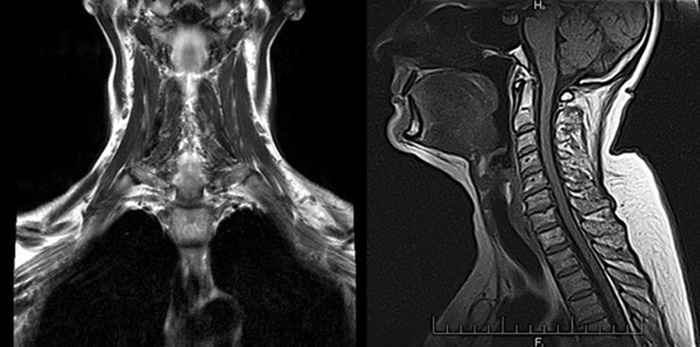

Сканы томографа представляют собой цифровые изображения в черно-белом формате. Съемку производят послойно под разными углами с небольшим отступом срезов друг от друга. Каждый снимок – это отдельный срез конкретного участка шеи. Благодаря высокому разрешению и детализации, на снимках видны даже микроскопические элементы следующих органов и тканей:

В особом режиме сканирования кости становятся менее заметными («прозрачными»), поэтому не перекрывают мелкие очаги воспаления или повреждения в соседних мягкотканных структурах.